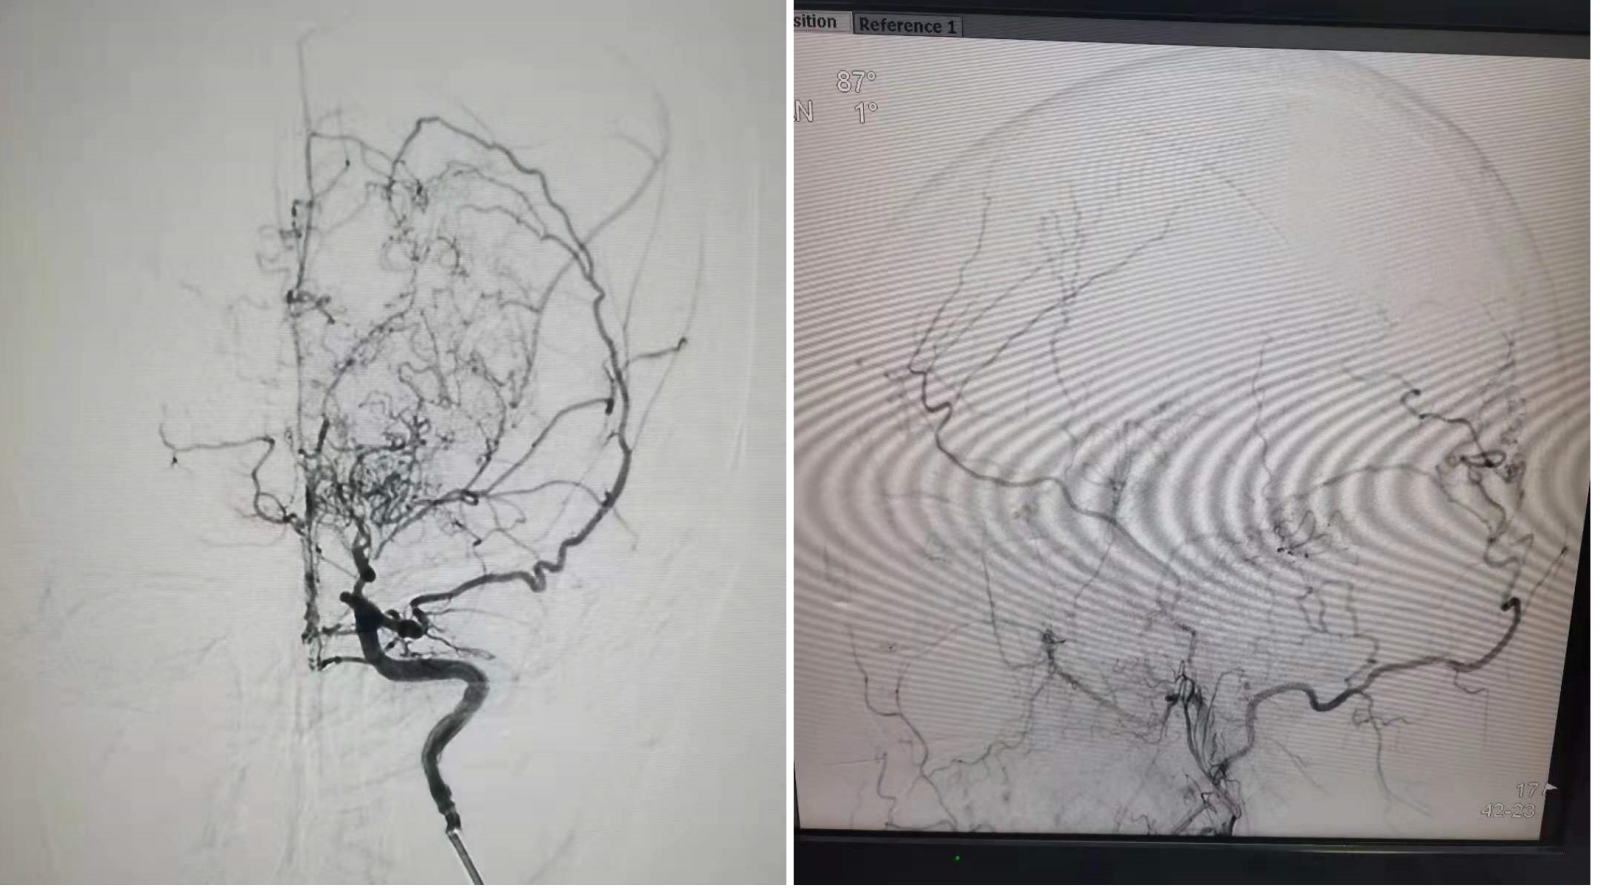

近日,我院东区神经外科团队成功完成一例“颞浅动脉-大脑中动脉搭桥+多因素联合贴敷术”。此手术是目前最先进的烟雾病治疗方案,也是我市自主完成的首例。

患者为中年女性,6个月前因脑出血而住院治疗,治疗过程中完善相关检查确诊为烟雾病。本次住院后经全脑血管造影进一步确诊,收治我院东区神经外科。神经外科团队共同讨论并拟定了周密的术前计划,在与家属充分沟通后,决定行“颞浅动脉-大脑中动脉搭桥+多因素联合贴敷术”。手术由神经外科主任医师赵程欣指导,主任医师张永哲主刀,主治医师李兵桥配合,手麻科副主任医师高飞主持麻醉。经过4个多小时紧张而有序地忙碌,手术顺利完成。此例手术难度极高,风险极大,不仅需要精湛的显微外科技术、高超的血管吻合技术和配套的高精尖设备做支撑,还要有复杂严格的围手术期管理。得益于我院医师们的精湛技术以及护士们的精心护理,患者术后恢复良好。

烟雾病又称自发性脑底动脉环闭塞症,是一组以双侧颈内动脉末端和(或)大脑前动脉、大脑中动脉起始部缓慢进展性狭窄以致闭塞,脑底出现代偿性异常血管网为特点的脑血管病。因其异常血管网在脑血管造影时形似“烟雾”,故称为“烟雾病”。烟雾病虽有个美丽的名字,但却暗含杀机,若不及时处理,约65%—82%的成年患者将多次发生脑缺血或脑出血,危及生命。